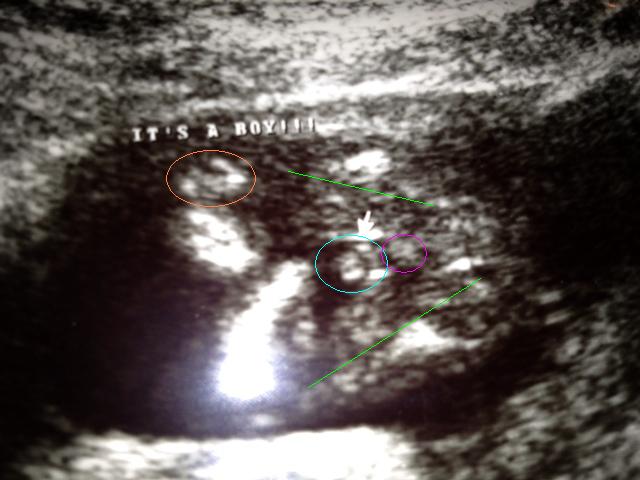

15w2d gender shot

Hello everyone! I am new to the gender dreaming site but I was hoping that you all could weight in on my 15w2d ultrasound shot. The tech said that she thought it could be a boy based upon the area that I circled in blue, but right behind the blue circle there are three white lines (circled in pink). Adminttedly I didn't noticed the white lines until my neighbor (a nurse) pulled the image up on her computer and blew it up really large.

I drew in the legs in with green lines and I also circled the hand in orange. If these are boy parts, aren't they rather large for 15w2d?!? I ask because the baby had the cord inbetween the legs for the majority of the scan and I'm wondering if it is indeed boy parts or a shot of the cord that looks like boy parts.

And without markups...

Attachment 7535